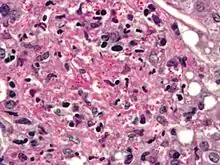

Histoplasmosis. PASD stain.

Histoplasma capsulatum can cause histoplasmosis in humans, dogs and cats. The fungus is most prevalent in the Americas, India and southeastern Asia. It is endemic in certain areas of the United States. Infection is usually due to inhaling contaminated air.